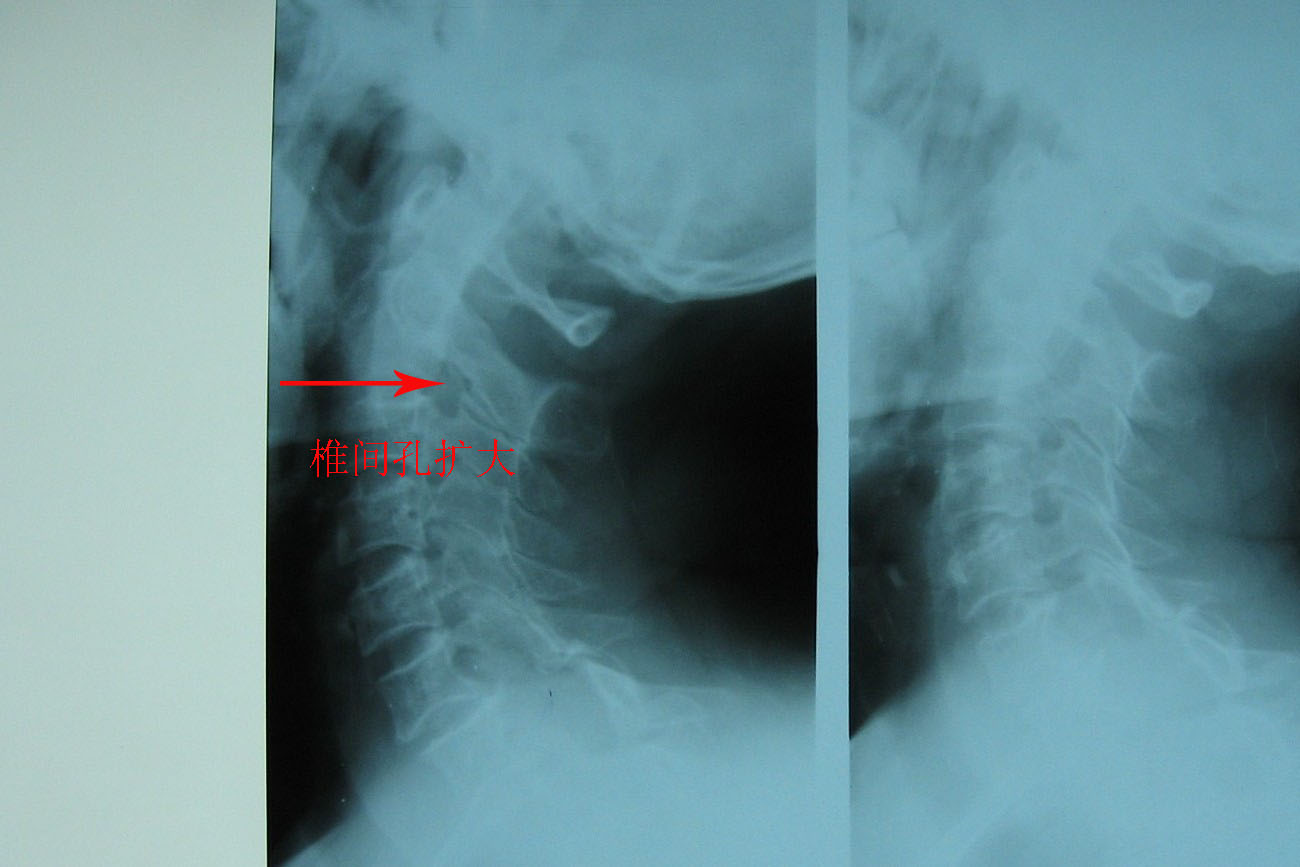

支持考虑:神经原性肿瘤。(右侧椎间孔扩大,椎板破坏,局部明显的软组织肿块,并与椎管 神经根关系密切。)

支持考虑:神经源性肿瘤(右侧椎间孔扩大,椎板破坏,局部明显的软组织肿块,并与椎管神经根关系密切)。